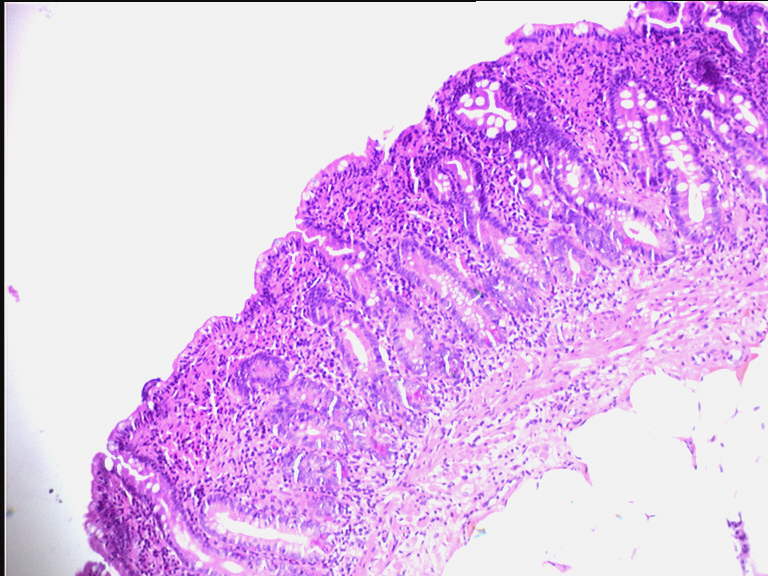

Maladie Coeliaque

Photographies de Coupes Histologiques :

Comparaison muqueuse duodénale normale et Atrophie villositaire (100N)